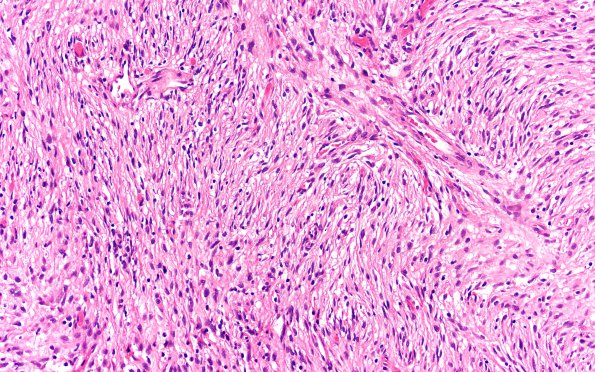

Washington University Experience | NEOPLASMS (NEURONAL) | Desmoplastic Infantile Ganglioglioma (DIG) | 4A4 DIG (Case 4) H&E 20X

Higher magnification image of the neoplasm shows significant collagen and fibrosis admixed with tumor cells. The spindle cells are arranged in fascicles or in a vaguely storiform pattern with dilated vascular spaces. (H&E)